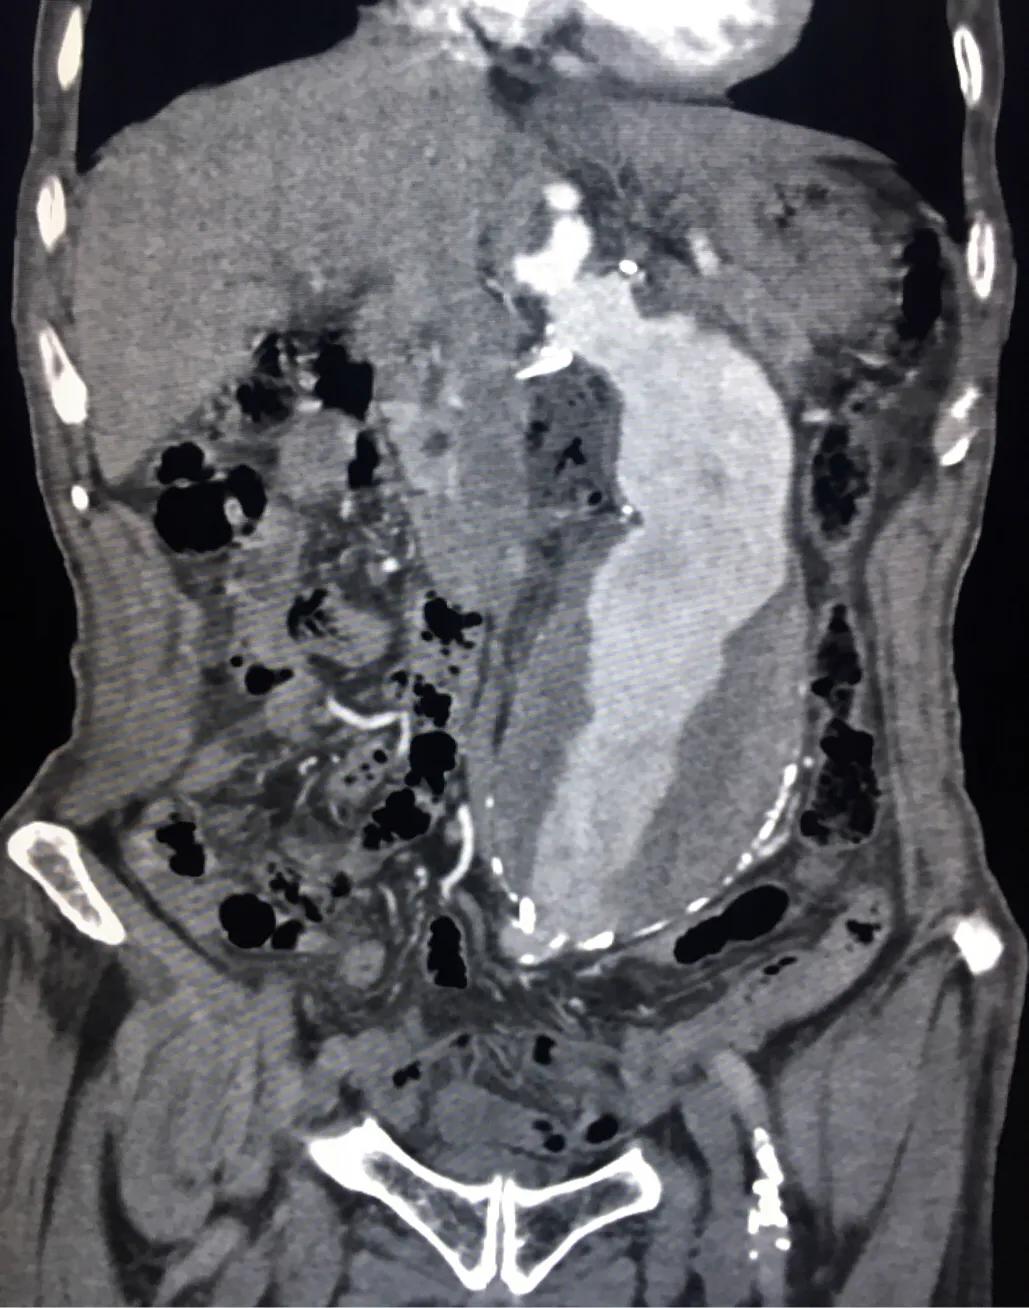

腹部CT明确,腹主动脉瘤样扩张,范围较大,最大横径接近快10厘米了,管壁可见不强化的血栓形成,诊断腹主动脉瘤。

腹主动脉瘤是指腹主动脉永久性的局限性扩张,当血管直径超过正常 50% 以上即可称为动脉瘤。通常情况下,腹主动脉直径 >3 cm 可以诊断为腹主动脉瘤。